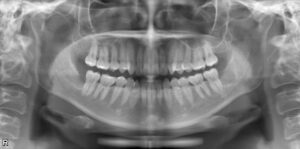

パノラマレントゲン写真

口腔内写真ではわからないところを検査するためのスクリーニング検査となります。

親知らずの位置や、歯周病の状態、過去の虫歯治療の痕跡などを見ることができます。